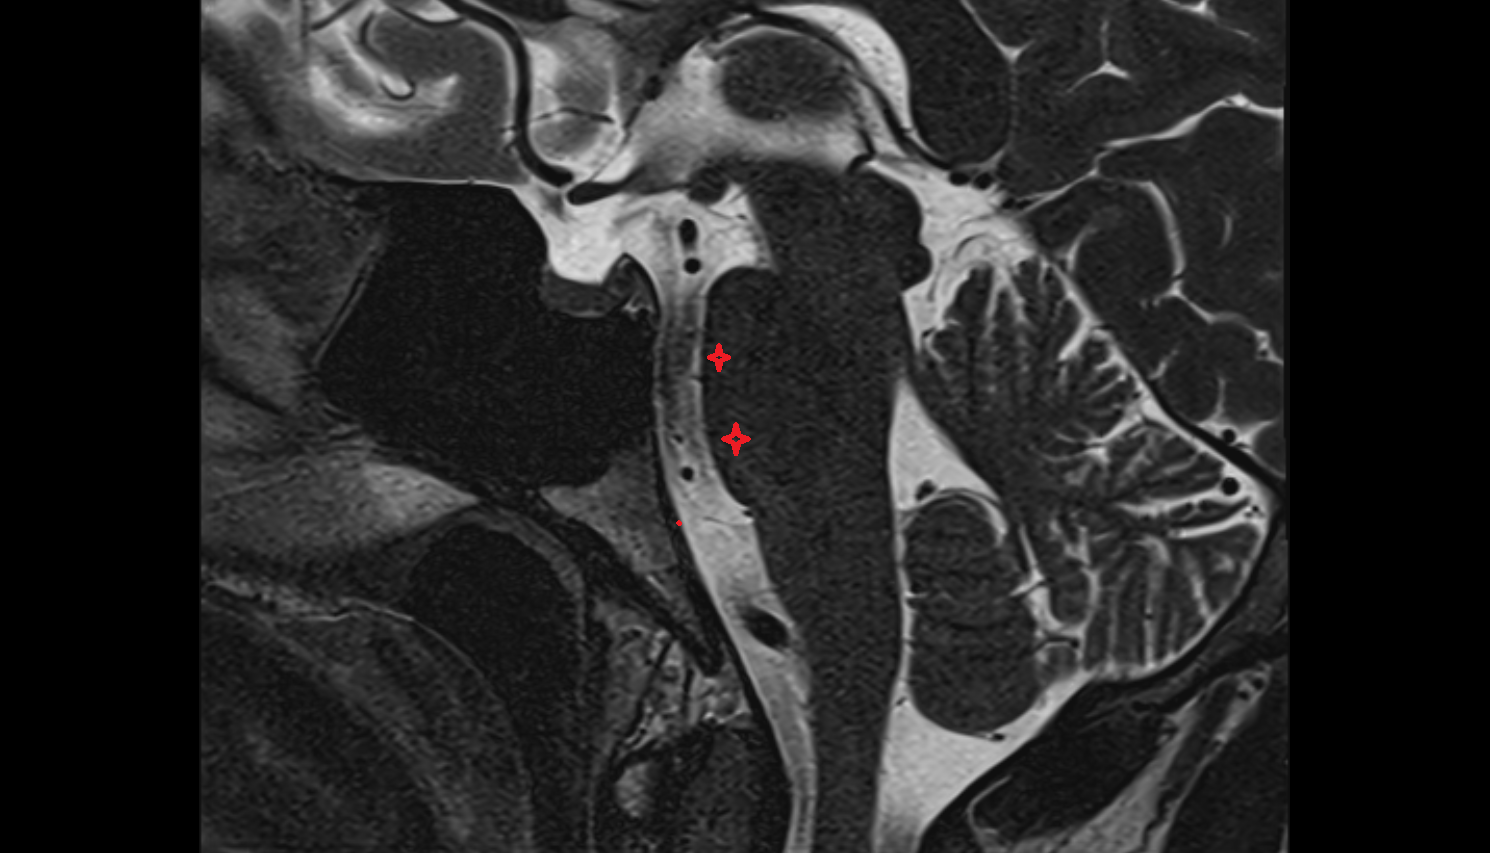

- Middle cerebellar peduncle